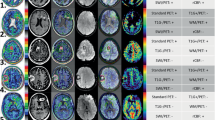

Three imaging features were found helpful for identifying nCET; “Bulky gray matter involvement”, “Around the rim of contrast-enhancement (Around-rim),” and “High-intensity on T1WI and low-intensity on T2WI (HighT1LowT2)” resulting in an nCET score = 2 × Bulky gray matter involvement – 2 × Around-rim + HighT1LowT2 + 2. The nCET score’s classification performances of two independent observers measured by AUC were 0.78 and 0.80, with sensitivities and specificities using a threshold of four being 0.443 and 0.771, and 0.916 and 0.768, respectively. The weighted kappa coefficient for the nCET score was 0.946.

Graphical abstract